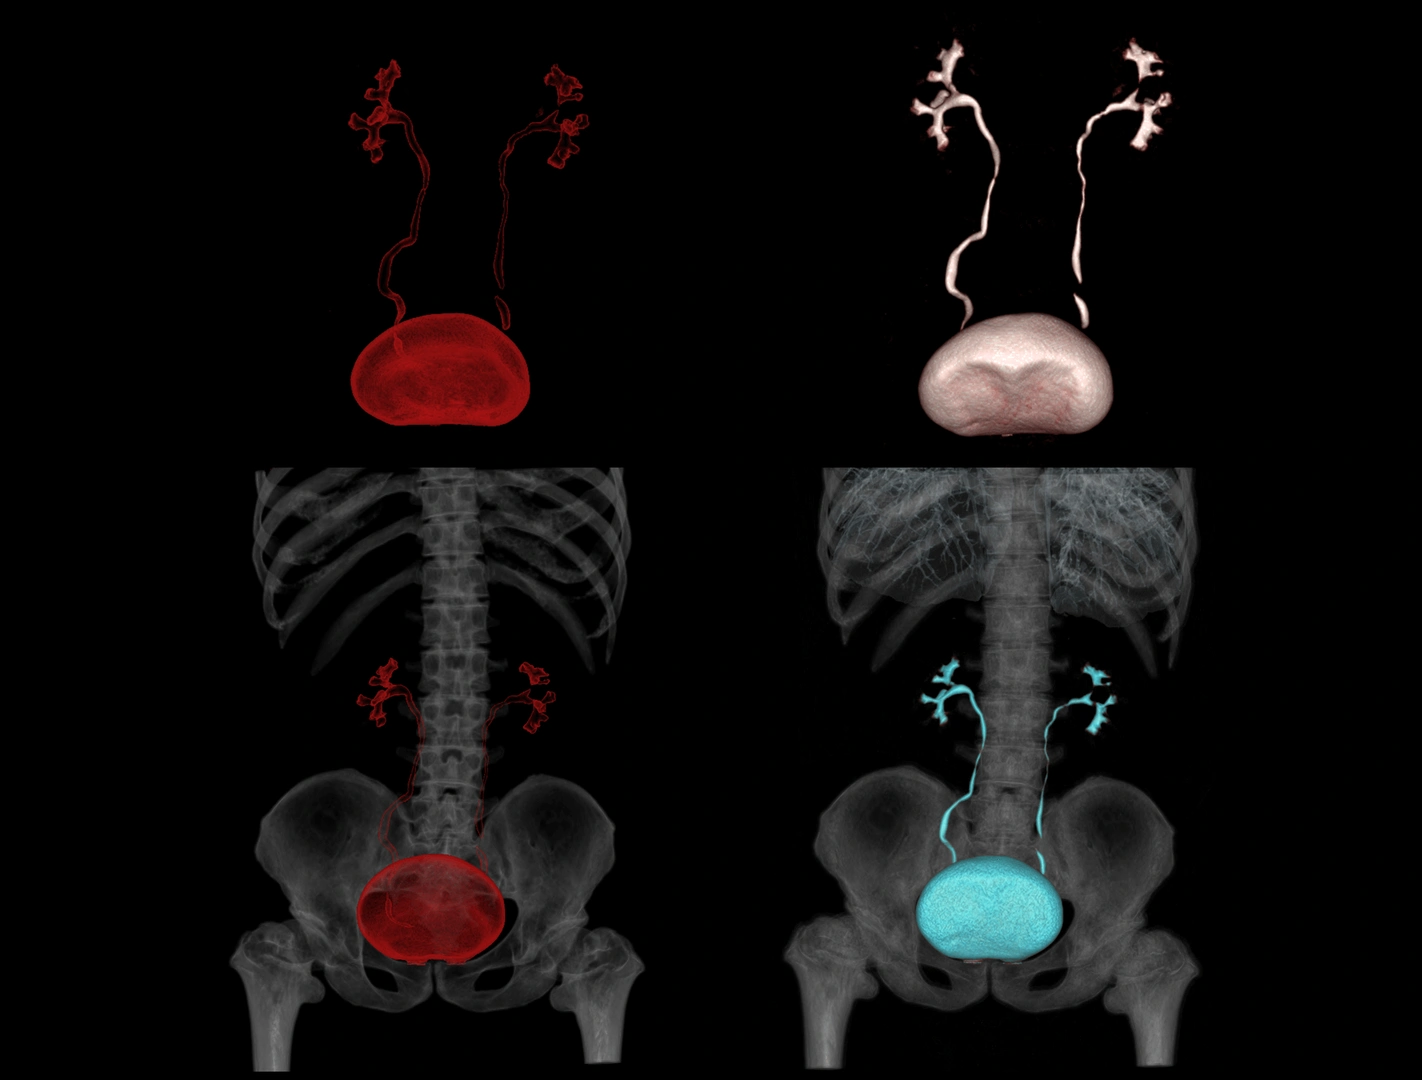

- Abdomen y pelvis: hígado, riñones, páncreas, aparato digestivo